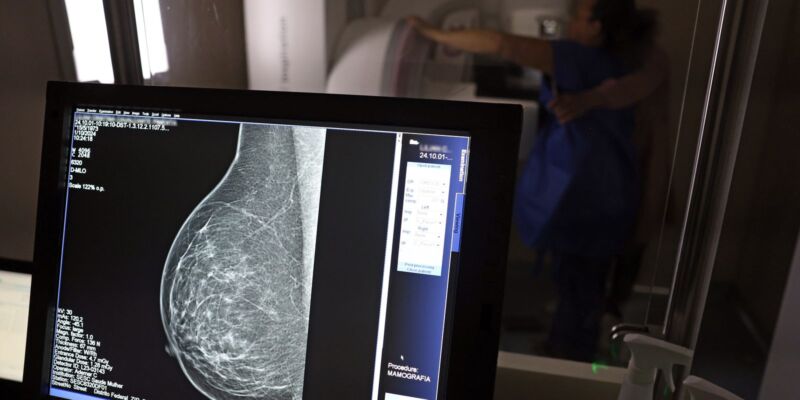

A partir de quantos anos se deve fazer a mamografia de rastreio, ou seja, como um exame de rotina, mesmo sem sintomas? Para autoridades públicas, como o Ministério da Saúde e o Instituto Nacional do Câncer (Inca), o ideal é que a mamografia seja feita a cada dois anos por todas as mulheres entre 50 e 69 anos. Algumas entidades médicas, como a Sociedade Brasileira de Mastologia (SBM), entretanto, recomendam exame anual a partir dos 40 anos.

Roberto Gil explica por que esses estudos consideram que os 50 anos são a idade certa para o início do rastreamento na população em geral: “Não estamos negando que mulheres abaixo de 50 anos tenham câncer de mama. Estamos falando que, abaixo dos 50 anos, acumulam-se outros problemas e o rastreamento populacional é menos eficiente. A mamografia é um exame de raio X, que vai ser mais efetivo na medida que a mama seja menos densa e que se tenha mais contraste na imagem, para não se confundir o parênquima normal com um nódulo. Então [antes dessa idade], aumenta muito mais a possibilidade de ter falsos positivos e ter que fazer mais exames. Posso fazer uma biópsia e ser mais difícil interpretar e levar a uma cirurgia desnecessária.”